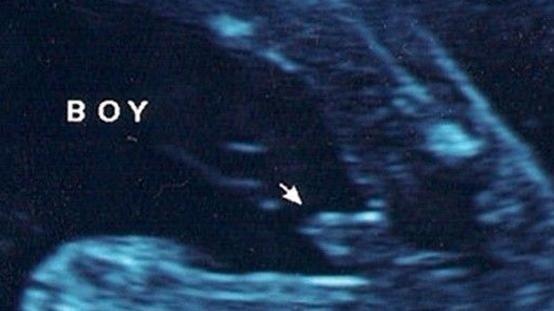

男宝宝B超图

男宝宝B超

"凸出的东西"是他的标记:你们看到圆圆的是DANDAN,如果看到圆圆的加小肠的就是全部JJ